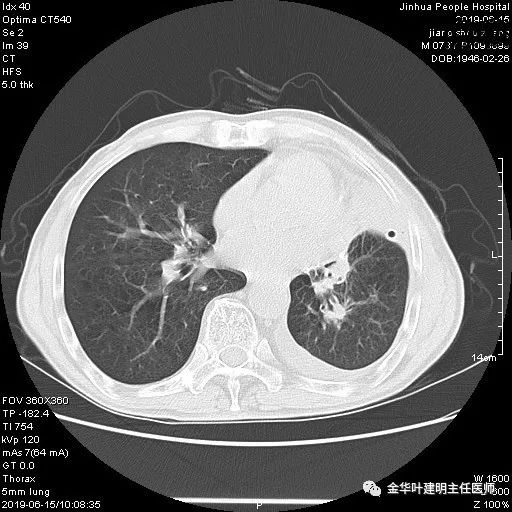

患者,男性,73岁,金华人。因“咳嗽咳痰伴胸闷2月,检查确诊左肺癌1周”入院。气管镜: 气管支气管内较多脓性分泌物,左肺上叶前段管腔新生物,局部活检、毛刷。气管镜病理:(左肺活检)鳞癌。阅胸部CT见左上叶开口处新生物,考虑需左上叶袖式切除及淋巴结清扫。具体CT表现如下:

考虑左侧大量胸腔积液,遂进一步胸部CT检查:

以上是肺窗表现,下面为纵隔窗影像: